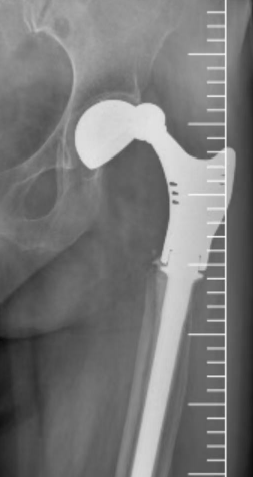

接诊后,北京积水潭医院郑州医院骨病与骨肿瘤科主任秦光华团队展开全面评估,影像学检查显示多重棘手问题:

人工髋关节脱位明确且假体松动明显,

患侧脱位后解剖结构紊乱,进一步增加治疗难度。

术前X线影像检查